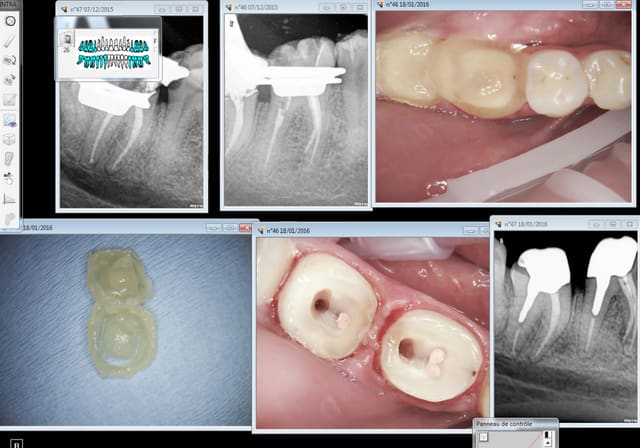

Ici en core + ic provisoire labo sur RTE ( on sort d'une pèche maous costaud) la définitive dans 6 mois.

Capture d e cran 2016 01 20 09.36 - Eugenol

Capture d e cran 2016 01 20 09.37 - Eugenol